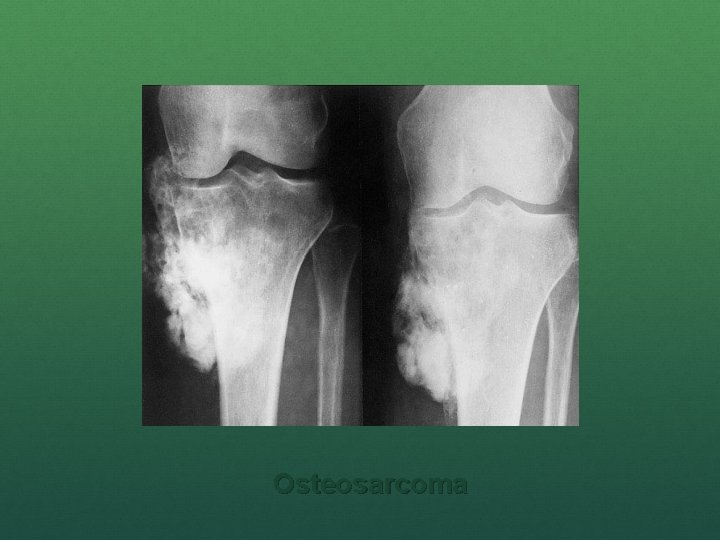

Osteosarcoma (Osteogenic sarcoma) It is a malignant mesenchymal tumor in which cancellous cell produce bone matrix. Most common primary malignant tumor of bone Occurs in all age group but has bimodal age distribution 75% occur in person younger than 20 years of age Second peak occur in elderly who have predisposing condition – Paget disease, bone infarct, prior irradiation Males> females

Usually arise from metaphysis of long bones of extremities, and almost 50% occur about the knee. Beyond the age of 25 years incidence in flat bones and long bones is almost equal.

Several subtypes of osteosarcoma are grouped according to – 1. Site of origin (intramedullary, intracortical or surface) 2. Degree of differentiation 3. Primary (underlying bone is unremarkable)or secondary to preexisting disorders. 4. Histological features (osteoblastic, chondroblastic, fibroblastic, telangiectatic, small cell and giant cell). The most common subtype arises in metaphysis of long bones and is primary, solitary, intramedullary and poorly differentiated. Grossly, Osteosarcoma are big bulky tumors that are gritty, grey-white, and often certain areas of hemorrhage and cystic degeneration.

Clinical features Localized pain and swelling Fast growing tumor Progressive weakness and weight loss Skin over the tumor is shiny and stretched with prominent veins Warm, tender and ill defined margins. Pulsatile tumor Movement of adjacent joint restricted due to mechanical obstruction and effusion. Regional lymph node enlarged only in 25 -30% cases. If distal neurovascular deficit present strongly suggest malignancy. Lung metastasis occur in 10 -12 months if left untreated.

n Classic X-ray findings: 1. 2. 3. 4. Codman's triangle (periosteal elevation) Sunburst pattern/Sunrays appearance Bone destruction Ill-defined margins